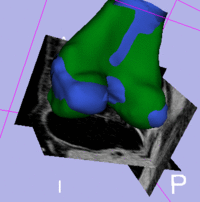

Registration Results

femur surface models before/after registration

The final goal is to align a segmentation prior model/atlas to aid in cartilage segmentation.

1. Input Surface: S02_femur

2. Target Surface: S01_femur